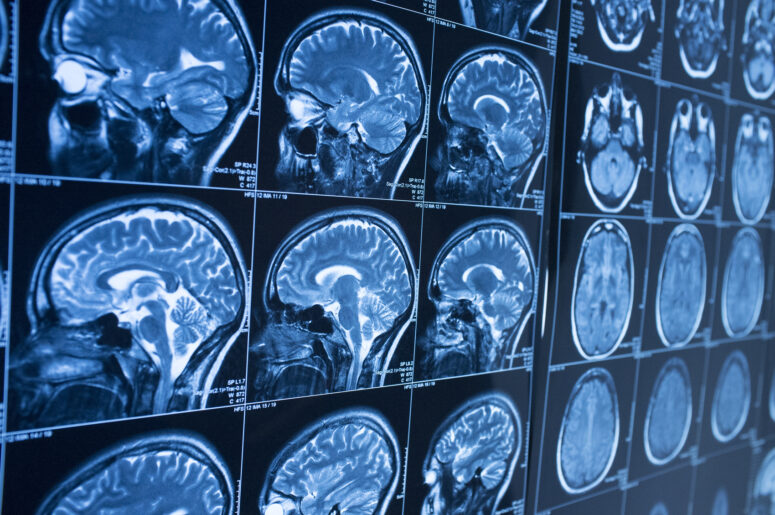

It is no secret that the brain is an exceedingly delicate organ. Unfortunately, every year in New York, countless individuals suffer injuries to their heads that result in long-term damage to their brains. No matter how small the impact may initially seem, if you hit your head, it is always advisable to seek immediate medical attention. The faster a brain injury is identified, the greater the chance that it may be possible for physicians to treat it and limit the damage sustained.

Most people are aware of the potential dangers of concussions. These injuries, caused by direct impact to an individual’s head, can have numerous serious consequences, some of which can take weeks or longer to manifest. Some of the warning signs include dizziness, nausea, loss of consciousness or any other cognitive impairment. If such symptoms develop, you should see a doctor as soon as possible.

Another form of brain injury about which many people are less aware are contusions. These are very similar to concussions, as this article on TBIs explains. However, the thing that identifies a brain injury as a contusion is the presence of a localized bleed. This is understandably dangerous and can have fatal consequences if any resultant clots are not removed.